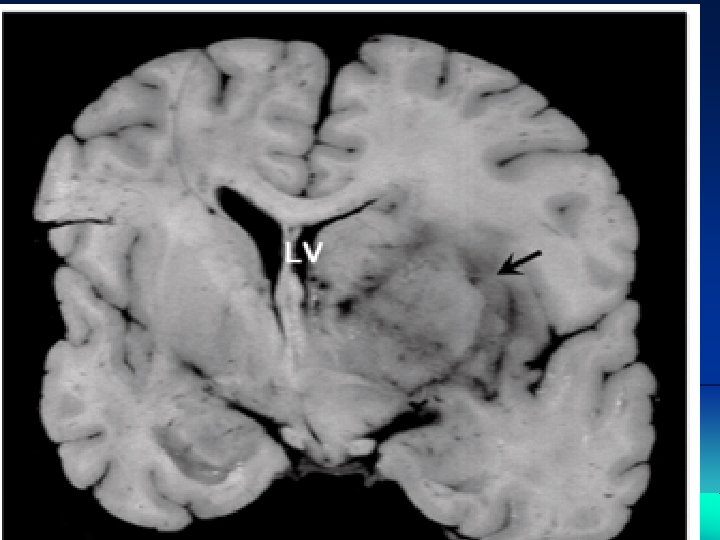

CNS lymphoma may affect people whose immune system is not working properly. for example, after organ transplants, or in people with HIV

primary CNS lymphoma. : The most common site for a CNS lymphoma is the cerebrum The areas of the brain

CNS lymphoma The symptoms and signs of CNS lymphoma are often related to increased intracranial pressure ( ICP ), e. g. headache, mental change, or focal neurological deficits Notably, only 5% of CNS lymphoma patients experienced inner ear symptoms such as vertigo, tinnitus or progressive hearing loss [9]. Thus, clinically, vertigo accompanied by progressive hearing loss rarely occurs in CNS lymphoma.